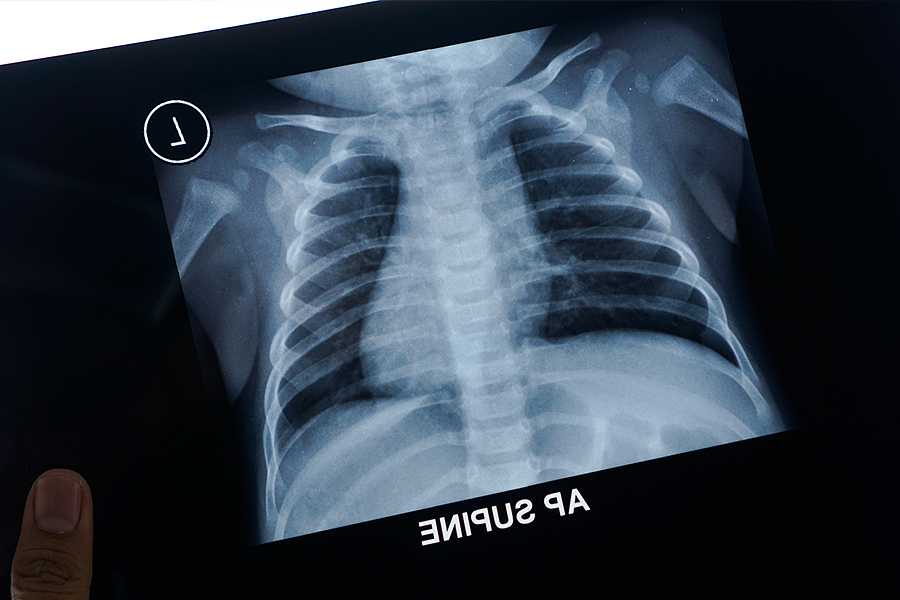

Пневмония у детей

В пульмонологической практике при классификации пневмоний учитывается специфика клинических проявления при той или иной форме патологии, обстоятельства заражения, морфологические признаки детских пневмоний, выявленные в результате рентгенографии; степень тяжести, пролонгированность, причины и условия возникновения воспаления лёгких.

По рентгеноморфологическим признакам детская пневмония ранжируется на очаговую (очагово-сливную), крупозную, сегментарную, интерстициальную.

Клиническая диагностика детской пневмонии строится на основе общих симптомов, аускультативных нарушениях в лёгких и данных рентгенологического исследования. Рентгенография лёгких позволяет обнаруживать очаги инфильтрации или интерстициации.